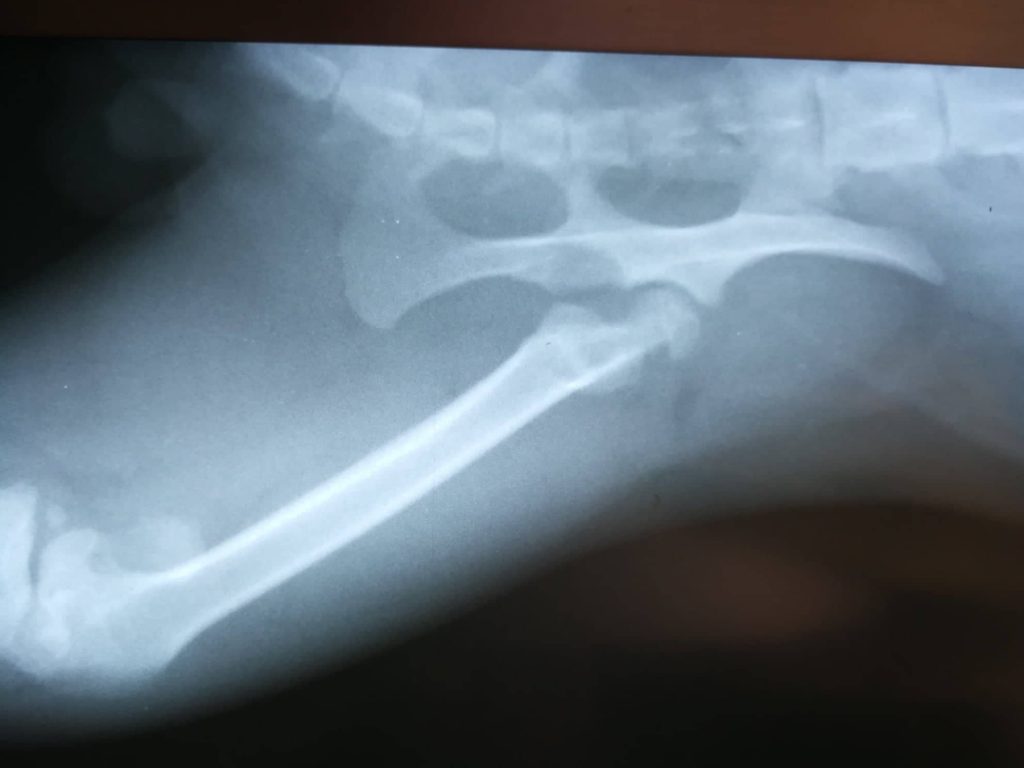

Rentgen ukázal, že Puzzle měl starou zlomeninu nohy a k tomu vykloubenou kyčel. Kocourek měl zal sebou jistě hodně bolesti… Dělali jsme vše pro to, aby vyhrál svůj boj a dostal svou šanci najít si novou rodinu a mít konečně milující páníčky.

Nejdřív bylo nutné Puclíkovi dát do pořádku kyčel. Operace dopadla dobře. Pak ale bylo potřeba ještě opravit zlomenou zadní packu. Pan veterinář kocourkovi nožku krásně zpevnil. Mysleli jsme, že to byla Puclíkova poslední překážka na cestě ke šťastnému životu plnému rozmazlování…

Teď už má ale Puzzlík cvičení konečně za sebou a mohl podstoupit důležitou operaci! Pan doktor Puzzlíkovu nožičku tentokrát zpevnil zvnějšku a vypadalo to dobře.